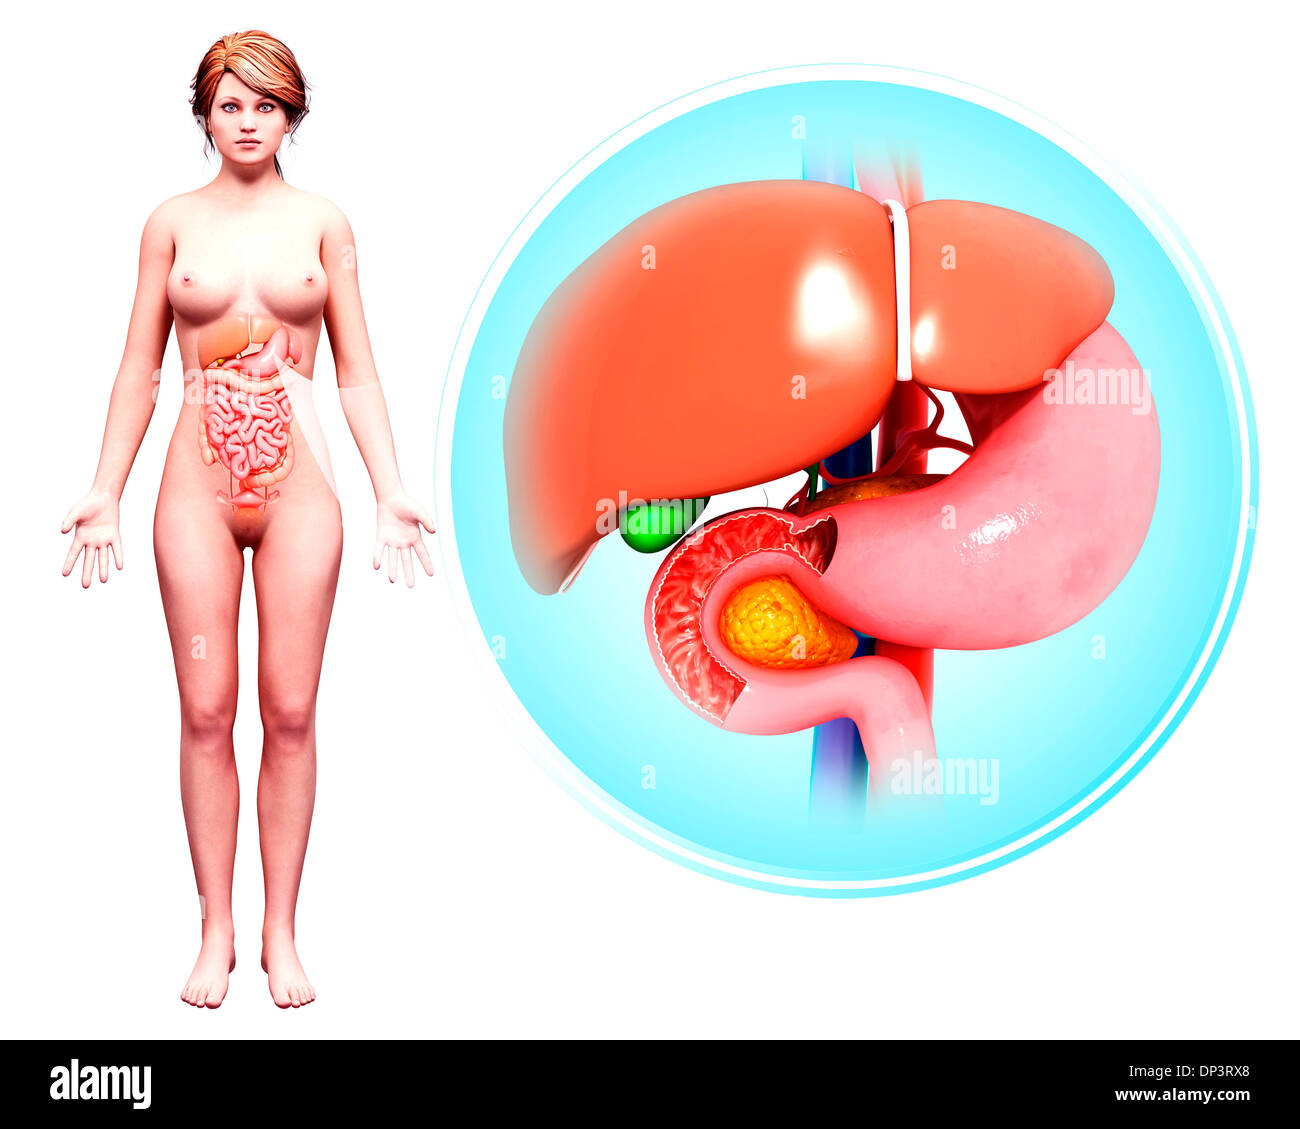

Système digestif humain, artwork Banque D'Imageshttps://www.alamyimages.fr/image-license-details/?v=1https://www.alamyimages.fr/systeme-digestif-humain-artwork-image65238160.html

Système digestif humain, artwork Banque D'Imageshttps://www.alamyimages.fr/image-license-details/?v=1https://www.alamyimages.fr/systeme-digestif-humain-artwork-image65238160.htmlRFDP3RX8–Système digestif humain, artwork

Système digestif humain, artwork Banque D'Imageshttps://www.alamyimages.fr/image-license-details/?v=1https://www.alamyimages.fr/systeme-digestif-humain-artwork-image65238055.html

Système digestif humain, artwork Banque D'Imageshttps://www.alamyimages.fr/image-license-details/?v=1https://www.alamyimages.fr/systeme-digestif-humain-artwork-image65238055.htmlRFDP3RPF–Système digestif humain, artwork